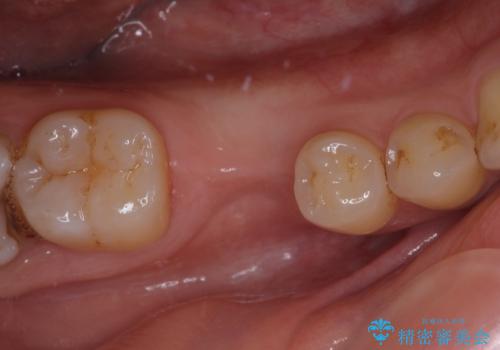

根管治療を行ったままの奥歯 オールセラミッククラウンによる補綴治療